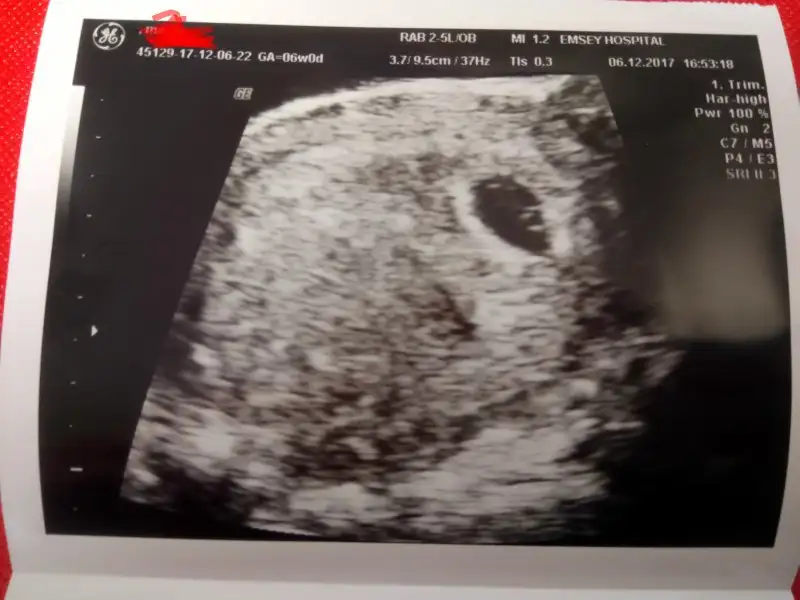

Ben göremedim kaç mm oldugunu ya bi bakar mısınız gebe bacılarEvet yazıyor hafta bilgisinin yanina 0 virgüllü bir deger

Burda degil kese görüntüsü ile beraber bir cikti daha verdi mi yoksa tek bu mu var elinde.Ben göremedim kaç mm oldugunu ya bi bakar mısınız gebe bacılaracaba bebek tam görünmediği için mi yok? Çünkü henuz sadece yolc sac görünüyor sanırım